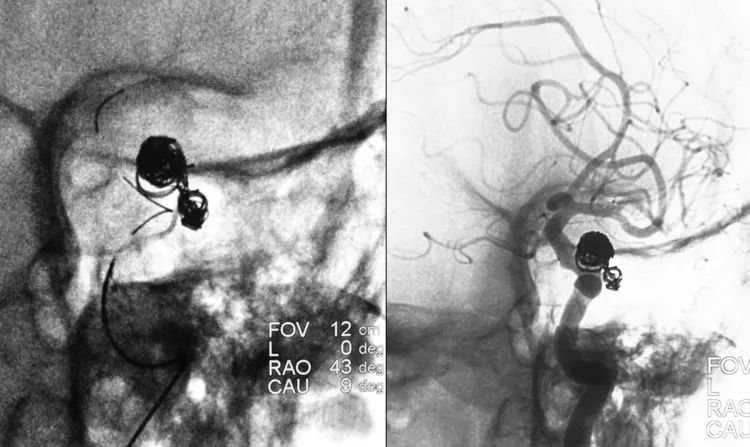

经甲管向小分叶内填入3枚弹簧圈(QC-4-8-3D,DELTAPAQ 10-3-10-CERECYTE,DELTAPAQ 10-2-8-CERECYTE):

经支架导管送入EnterPrise支架(4.5-28),跨瘤颈释放于左颈内动脉虹吸部;在支架保护下,经乙管向大分叶内填入7枚弹簧圈(PRESIDIO 10-7-30-CERECYTE,PRESIDIO 10-6-26-CERECYTE,QC-6-20-HELIX,PRESIDIO 10-5-17-CERECYTE,QC-5-15-3D,QC-4-10-HELIX,QC-3-8-3D),并将瘤颈呈马鞍状封闭:

术后左颈内动脉工作位造影显示动脉瘤完全栓塞: